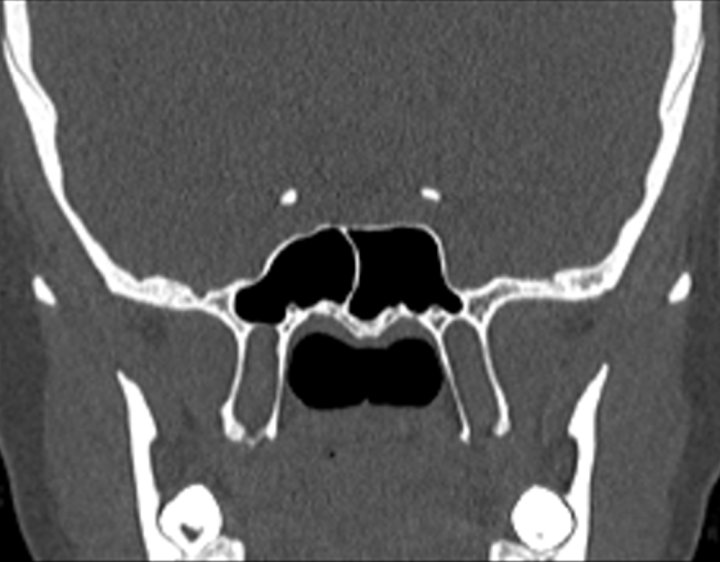

Click any image for labels.